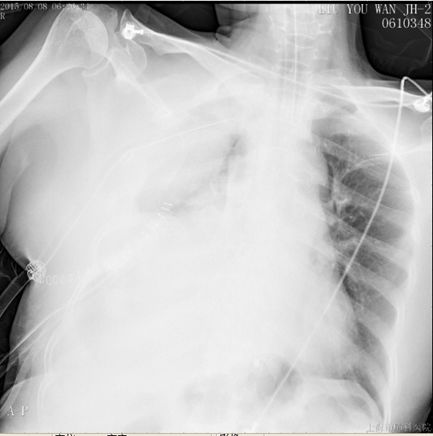

描述:溶栓2h后,胸引量:400ml

描述:溶栓18h后,胸引量:1700ml

溶栓18h后,胸引量明显增多,同时提醒胸腔内大量血肿,因此于术后第五日,予以全麻下行VATS剖胸止血术,手术时间1.5h,术中失血600ml,输血球2单位,术后带气管插管入ICU。止血术后第一日胸引量450ml,复查血气正常,予以拔除气管插管,SPO2 96%,HR 81bpm,BP 135/88mmHg。